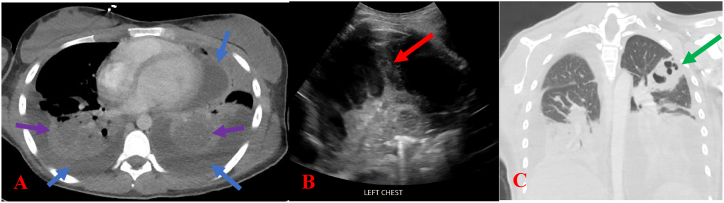

On day three of hospitalization, repeat CT scan of the chest showed bilateral multifocal, necrotizing pneumonia, pleural effusions with loculations, cavitary abscess, left empyema, and mediastinal lymphadenopathy (Fig. 3). CT of neck showed right palatine tonsil and thyroid abscesses (Fig. 2). No thrombi of the bilateral internal jugular veins were identified. Otolaryngology evaluated her and attempted bedside drainage, which was unsuccessful. Daily chest radiographs showed worsening multifocal pneumonia.

Fig. 3.

Image A is an axial CT scan of the chest with intravenous contrast, which demonstrates bilateral pleural effusions (blue arrows) and bilateral pulmonary consolidations (purple arrows). Image B is an ultrasound of the chest, which shows bilateral hypoechoic pleural effusions with thick septations (red arrow) consistent with empyema. Image C is a coronal CT of the chest with intravenous contrast shows a cavitary left upper lobe mass (green arrow) concerning for cavitary/necrotizing pneumonia. (For interpretation of the references to colour in this figure legend, the reader is referred to the Web version of this article.)